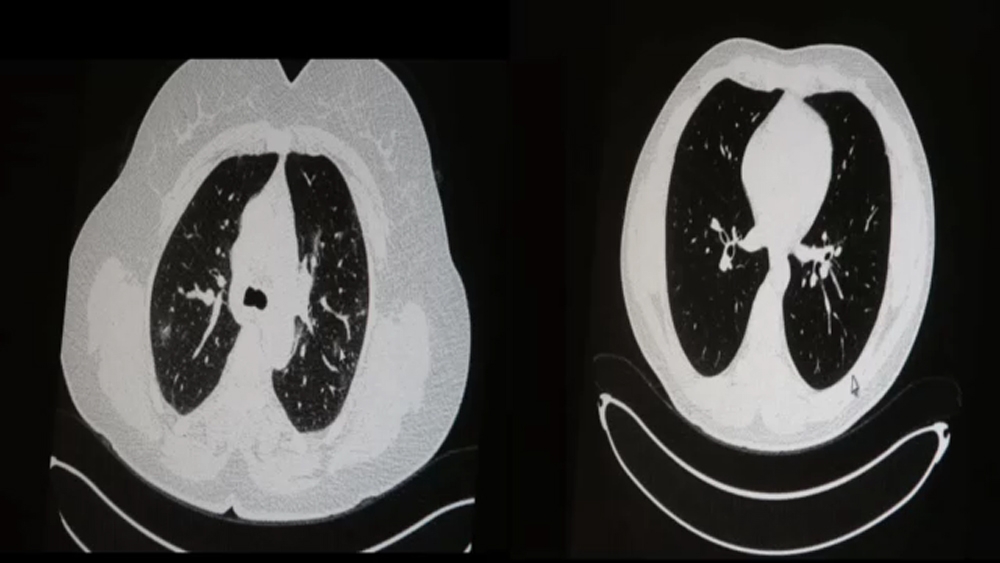

Sağlık